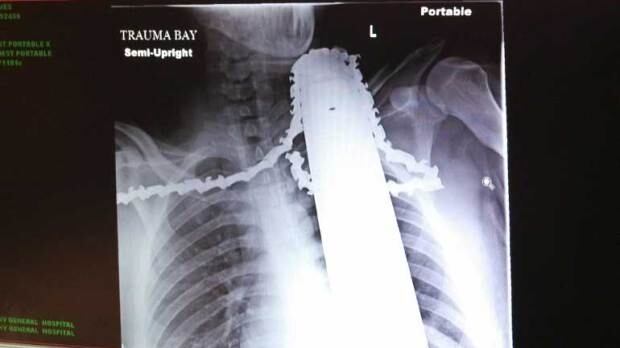

Man survives chainsaw injury to his neck